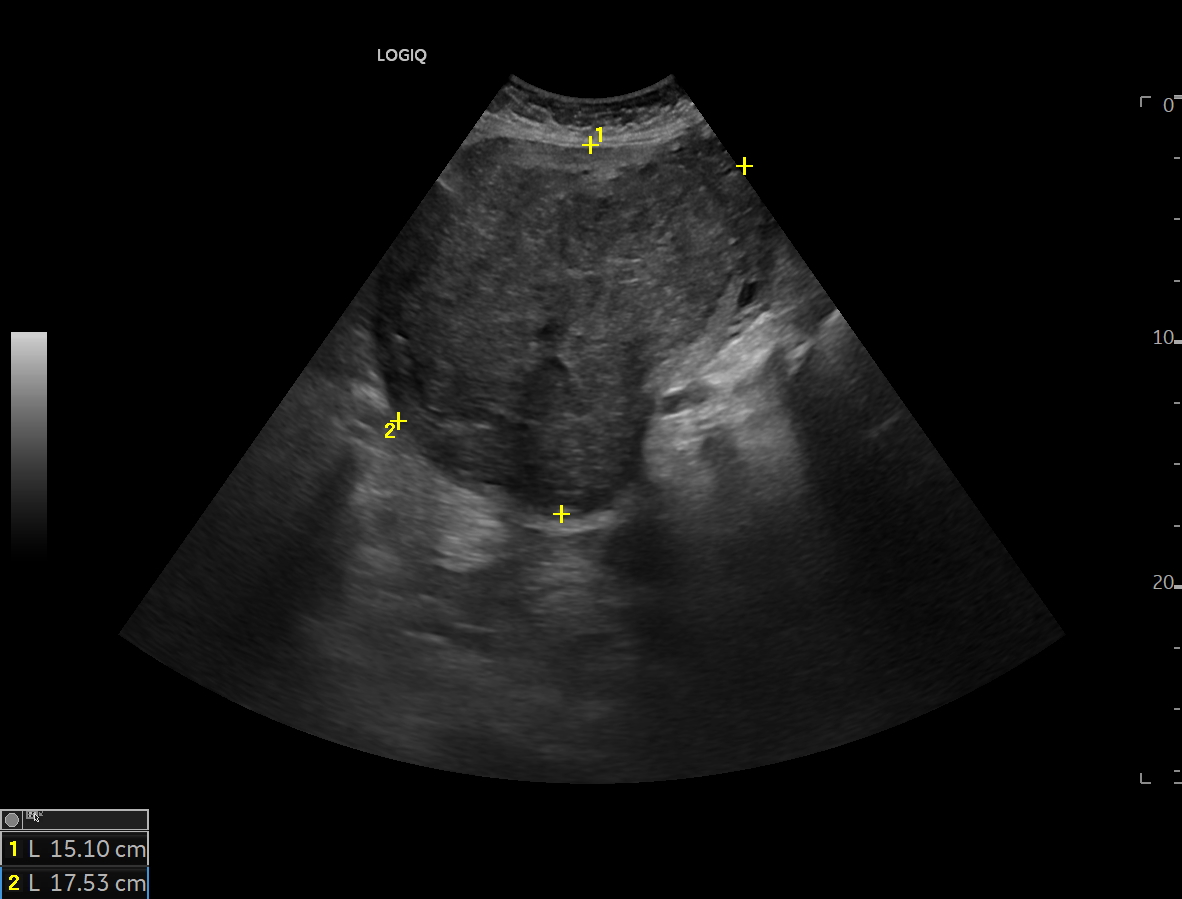

Se realiza ecografía clínica, en la cual se encuentra masa abdominal de 20x20 cm.

Se realiza ecografía clínica donde se aprecia masa abdominal de 20x20 cm sin identificar origen, porque posteriormente se solicita interconsulta con ginecología, la cual le realiza RMN, la cual da el siguiente resultado:

Masa hipogástrica compatible con leiomioma uterino, con focos de degeneración quístico-necrótica e hialina.